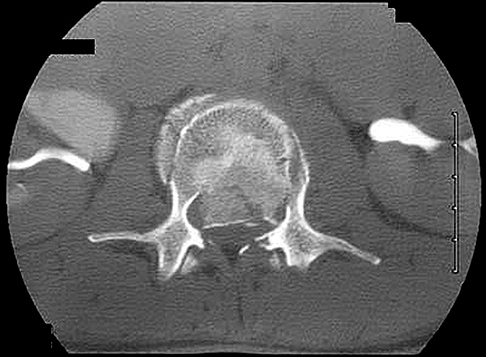

Figures 1 through 3 show sagittal and axial MRIs and a radiograph from a

77-year-old woman with leg pain when standing and walking of 1 year duration. The pain improves when she leans forward. She has been in physical therapy, taken oral analgesics, and had epidural injections with minimal relief. What is the best next step?

The patient has lumbar stenosis of L2-3 and L3-4. She has no spondylolisthesis or instability. For her condition, spinal fusion plays a minimal role. She has no evidence of instability, and her condition can be addressed through laminectomy only. No role exists for microdiskectomy, because her disease results from a combination of ligamentum flavum hypertrophy and facet hypertrophy.